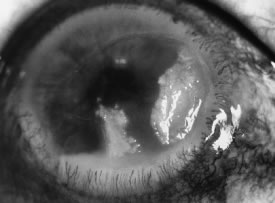

Candida infection typically produces epithelial ulceration, focal necrotizing stromal inflammation, moderate cellular infiltrate and edema in the adjacent stroma, and mild or moderate iritis in the early stages, indistinguishable from bacterial keratitis (Figs. 15, 16, and 17). Fungal elements cannot be detected by biomicroscopy. If untreated, the keratitis evolves to produce dense suppuration and necrosis of the deep stroma. Although multifocal suppuration may develop in polymicrobial keratitis, there is no distinctive sign of mixed Candida and bacterial infection (Fig. 18).

Fig. 17. C. albicans in a 21-year-old woman. Topical proparacaine hydrochloride abuse. Epithelial and stromal ulceration. Note the dense, white area of necrotizing stromal keratitis.

Fig. 18. C. albicans and Streptococcus keratitis in a woman following chronic application of corticosteroid eye drops. Note the separate area of suppurative keratitis. Both organisms were isolated from the separate foci.